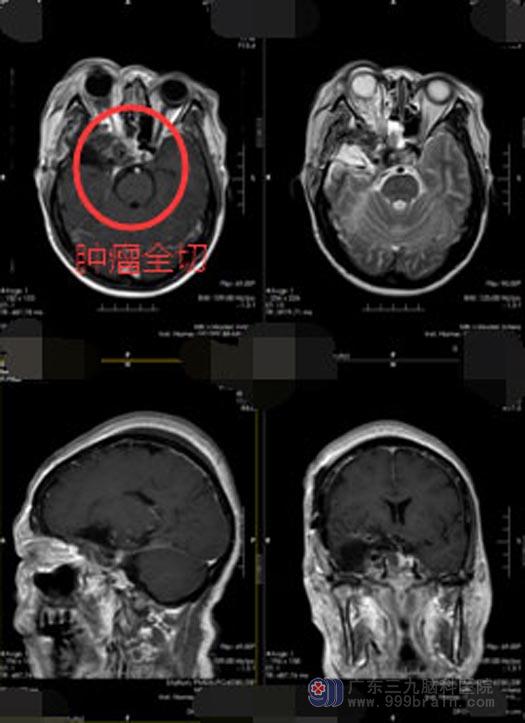

术中发现肿瘤位于鞍旁海绵窦区、鞍区、蝶窦、右侧眼眶,血管丰富,暴露左侧桡动脉及右侧颈部颈内动脉,行颅内外高流量搭桥手术(高流搭桥是指通过选择增加供血动脉或受血动脉血管直径以增加脑血供,其旧经移植血管吻合,血流在 80-90mmin 左右或以上)。将肿瘤从颈内动脉上完美分离,全切肿瘤并保护好了颈内动脉。手术顺利。